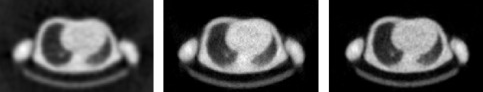

Figure 4 shows the reconstructions of a 10 min transmission scan. The same sinogram has been reconstructed with filtered backprojection, ML and MAP. Because the scan time is fairly long, image quality is reasonable for all algorithms.

Figure 5 shows the reconstructions of a 1 min transmission scan obtained with the same three algorithms. In this short scan, the noise is prominent. As a result, streak artifacts show up in the filtered backprojection image. The ML-image produces non-correlated noise with high amplitude. As argued in section Regularization, this can be expected, since the true number of photons attenuated during the experiment in every pixel is subject to statistical noise. And if that number is small, the relative noise amplitude is large. The MAP-reconstruction is much smoother, because the prior assigns a low probability to noisy solutions. This image is a compromise between what we know from the data and what we (believe to) know a priori.

Figure 4:Reconstruction of a PET transmission scan of 10 min. Left: filtered backprojection; Center: MLTR; Right: MAP (Maximum a posteriori reconstruction).

Figure 5:Reconstruction of a PET transmission scan of 1 min. Left: filtered backprojection; Center: MLTR; Right: MAP (Maximum a posteriori reconstruction).